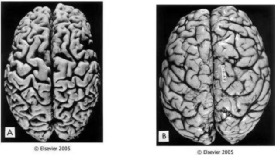

Ø影像“透视”大脑

MRI/CT:查看脑萎缩程度,排除脑梗或肿瘤